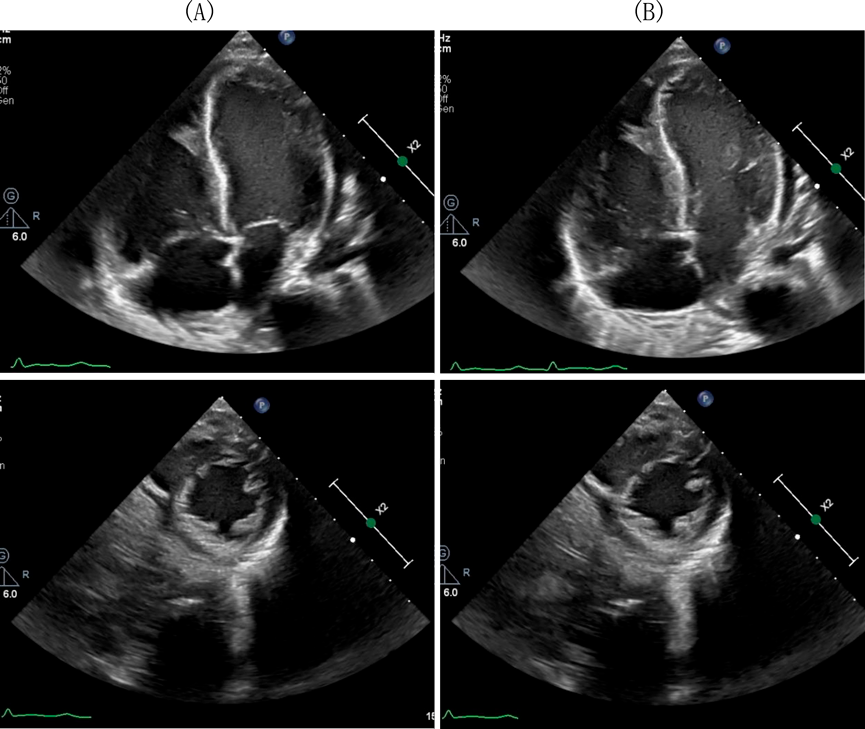

来院時の経胸壁心臓超音波(Fig. 3)で,両心収縮機能低下と軽度心嚢液貯留を認め,特に心尖部の心収縮性低下が著しかった.急性心筋炎を疑いガンマグロブリン(以下IVIG)(2 g/kg)単回投与とプレドニゾロン(以下PSL)(2 mg/kg/日)投与を開始し,心不全治療としてフロセミド(1 mg/kg/日),スピロノラクトン(1 mg/kg/日),ミルリノン0.4γを投与した.第7病日より後負荷の軽減と心筋線維化の予防のためエナラプリルマレイン酸を0.05 mg/kg/日より開始し,0.2 mg/kg/日まで漸増した.ミルリノンは第27病日で投与終了とした.血液検査で心筋逸脱酵素が低下したためPSLを漸減し,第7病日に中止した.その後末梢血中の好酸球分画が第9病日:5%(WBC 10,600, 530/µL),第11病日:13%(WBC 10,600, 1,380/µL)と上昇し,CK, CK-MB, AST, Troponin値も上昇した.EMCを強く疑い,第11病日よりPSL(2 mg/kg/日)投与を再開した.同日の経胸壁心臓超音波(Fig. 4)で右室心尖部に巨大血栓を認めたため,ヘパリン静脈内持続投与に加え,ワルファリン(0.1 mg/kg/日)の内服も開始した.第13病日には血栓は消失し,胸部CTで肺動脈内にも血栓はなかったため,第16病日にヘパリン持続投与を中止し,アスピリンの内服を追加した.第20病日よりPSLを内服に切り替え,第34病日より漸減開始した.好酸球数,CK, CK-MB, AST, Troponin Tの推移を確認しながらPSLを6 mg/日(0.4 mg/kg/日)まで減量した.減量後に心機能の悪化や筋逸脱酵素の上昇はなく経過したため第81病日に退院した.退院後3日より左眼の焦点が合わず,退院後7日に近医眼科を受診し,左眼外斜視と診断された.他の外眼筋麻痺はなかった.退院後9日より歩行困難となり,退院後11日に近医を再診した.左外斜視に加え,右上眼瞼下垂を認め,MGが疑われたため退院後17日に入院した.左眼球斜視,右上眼瞼の軽度下垂,動揺性歩行とGowers徴候を認めた.エドロホニウム試験で眼瞼下垂が改善し,反復刺激試験でWaningが再現性を持って確認され,全身型MGと診断された.胸部CT,非造影MRIでは胸腺腫はなく,骨盤~下肢骨格筋MRIでも筋炎を疑う所見はなかった.自己抗体に関しては抗アセチルコリン(AChR)抗体,抗Musk抗体,抗横紋筋抗体は陰性,筋炎特異的自己抗体としてJo-1,ARS,MDA5,Mi-2,TIF-γ,ミトコンドリアM2抗体も全て陰性であった.PSL(2 mg/kg/日)の隔日投与,IVIG(400 mg/kg/日)の5日間投与に加え,タクロリムスを開始し,症状が改善したため退院した.その後も近医にて加療中でMGの治療経過中に心筋炎の再燃はなかった.

Fig. 3 Echocardiography on admission

(A) Diastolic phase. (B) Systolic phase.